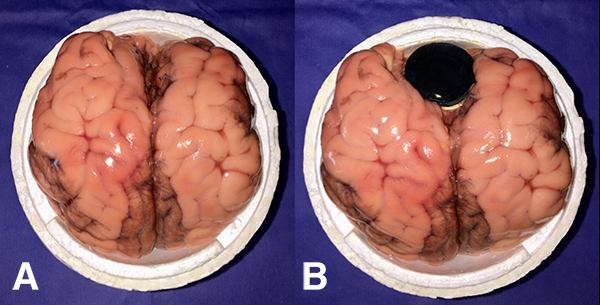

El modelo consiste en la utilización de un cerebro bovino (de preferencia utilizar la pieza completa) (fig. 1) y de pequeñas unidades de membrana amniótica, que se colocan envolviendo las tapas de botellas de plástico, para permitir la fenestración y dilatación de la misma (fig. 2 a-b). Éstas se disponen dentro de un recipiente esférico de poliestireno expandido (fig. 3 a-b), el cual se fenestra en la parte superior para permitir el ingreso del endoscopio. Para poder utilizar el monopolar debe colocarse dentro del recipiente el terminal del cable, que proviene de la consola, directamente en contacto con el tejido cerebral (fig. 4). Finalmente cerramos la esfera de poliestireno expandido y la llenamos por completo con solución fisiológica o agua corriente (fig. 5).

Para realizar la unidades de membrana amniótica utilizamos tapas de plástico color negro las cuales tapizamos del lado cóncavo con un fragmento de membrana amniótica de 5x5 cm. Para mantener la tensión utilizamos una banda elástica (fig. 2 b). Debemos rellenar la cavidad que quedó entre la tapa y la membrana amniótica con agua o solución fisiológica para lograr el medio acuoso que se encontrará una vez fenestrada la membrana y que simula el piso del III ventrículo (fig. 6). Para concluir colocamos la esfera sobre otro recipiente que sirve como base de sustentación y en la parte superior, donde teníamos las dos fenestras, colocamos dos trocares para el ingreso del endoscopio (no son requisito absoluto). Se utilizan dos entradas para duplicar el número de ejercicios (fig. 7). Este modelo innovador permite la biopsia y coagulación de tejidos (fig. 8) y la dilatación de membranas simulando un ejercicio de tercer ventriculostomía endoscópica.

Figura 3: Recipiente de poliestireno expandido. A) La imagen muestra el cerebro bovino colocado dentro del recipiente. B) Resultado final luego de colocar el cerebro bovino junto con la tapa con membrana amniótica.